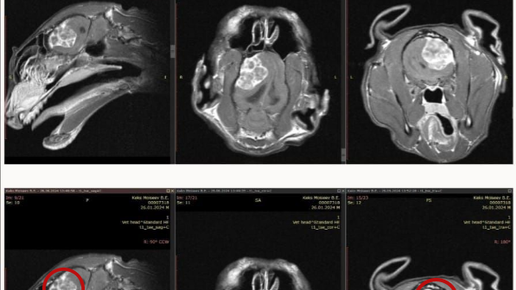

Котик Кекс поступил к нашему неврологу, нейрохирургу Элбакяну Арману Карленовичу по направлению коллег из другой клиники. У владельцев были жалобы на манежное движение в течение двух месяцев, то есть Кекс ходил кругами, динамика была отрицательная На приеме котик был апатичен с признаками возможной головной боли. Понять, болит голова или нет, мы точно не можем, но определенные поведенческие изменения позволяют делать подобные предварительные заключения. По результатам неврологического осмотра, выявленные нарушения свидетельствовали о неком поражении головного мозга...